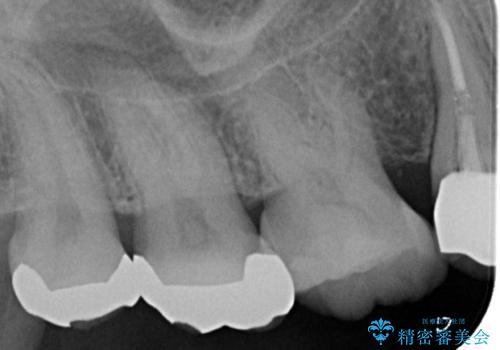

- 右上の歯に異和感があるとの事で来院した患者様です。

検査の結果、歯根破折が認められたため、抜歯即時インプラント(1DAYインプラント)を行いました。